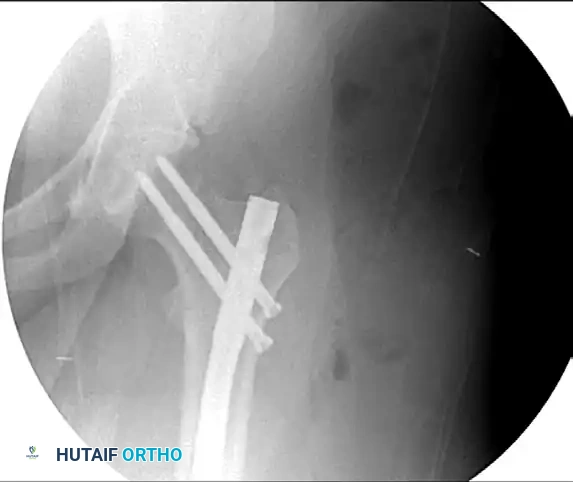

Figure 55-63A: Preoperative radiograph of a femoral shaft fracture. The subtle nondisplaced femoral neck fracture was initially missed.

Figure 55-63B: Intraoperative fluoroscopic view after placement of an antegrade intramedullary nail. Note the appearance of the proximal femur.

Figure 55-63C: Intraoperative fluoroscopic view after range of motion of the hip under live fluoroscopy reveals the previously occult femoral neck fracture.

Figure 55-63D: Intraoperative fluoroscopic view after removal of the standard proximal interlocking screw, adjustment of the nail, and successful placement of reconstruction screws.